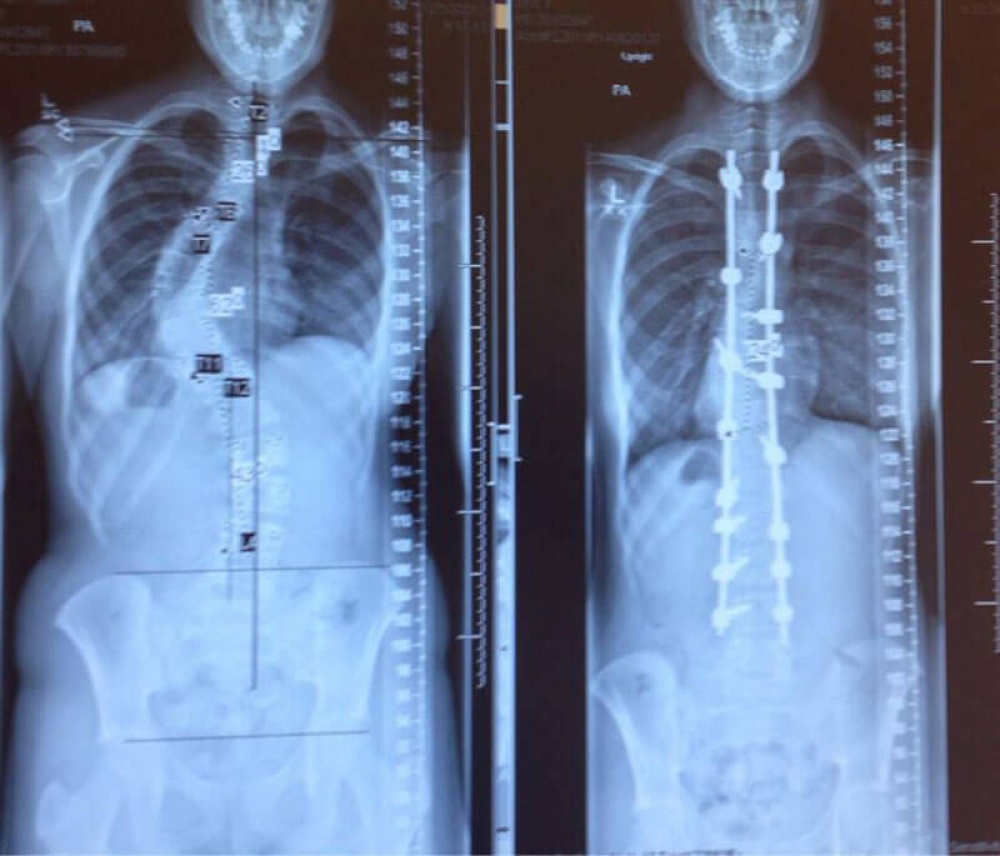

4. Хребет одного і того ж людини до і після лікування сколіозу.